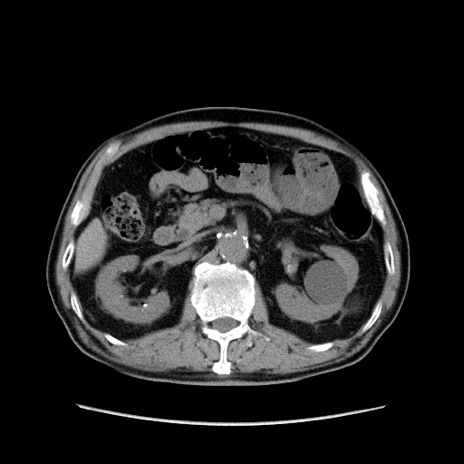

症例24(横断像)

【症例】80歳代男性

【主訴】左側腹部痛、嘔吐

【現病歴】本日早朝より左腹部に痛みあり。昼頃嘔吐認めたため、救急要請。

【既往歴】直腸癌(Mile手術)、胆摘

【身体所見】意識清明、BT 35.9℃、BP 221/93mmHg、SpO2 97%(RA) 、腹部:左ストーマ周囲に限局性の腹部膨隆あり。 膨隆部自発痛・圧痛あり・軟。

【データ】WBC 7700、CRP 0.09